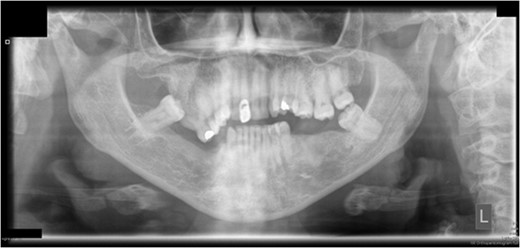

Preoperative orthopantomograph showing expansion of the right maxillary tuberosity.

The operation planned was a Le Fort I osteotomy with a right posterior segment osteotomy, which would set back the upper incisors by 6 mm, impact the upper left second molar by 4 mm and impact the posterior segment from the upper right first premolar (by 5 mm) to the upper right first molar (by 12 mm). No forward movement of the maxilla was planned. The segmental osteotomy was performed following down fracture of the maxilla and the final occlusion was aligned to a full coverage occlusal splint. The right descending palatal artery was sacrificed.

Craniofacial dysplasias may represent areas of anatomical variation where the blood supply may be susceptible to disruption. Although the patient had a biopsy showing normal bone, the maxillary tuberosity was expanded and hyperplastic clinically. This in itself would not however have accounted for the degree of avascularity seen in this case.